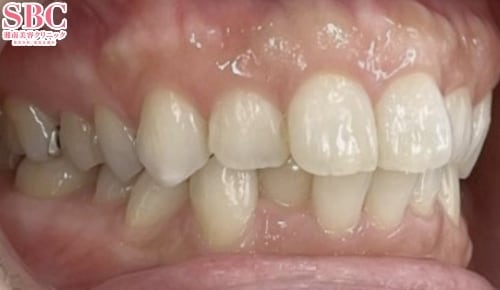

横から見ると重なりが目立ちます・・・

段差・重なり解消して綺麗に並びました★

上下の段差が気になるとのことで、インビザラインGoで矯正治療をした症例になります。